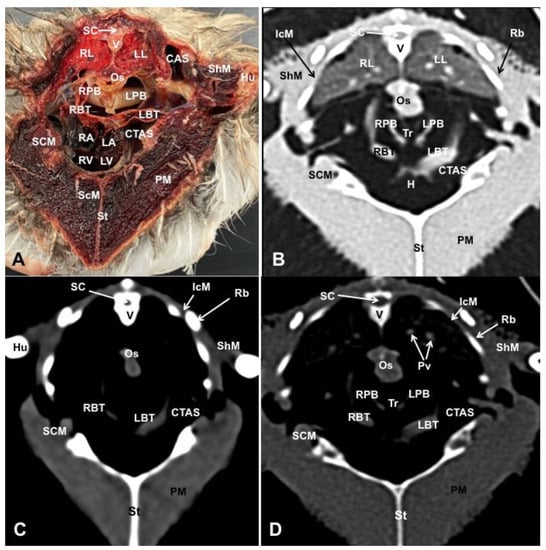

3.1. Anatomical Dissections and Cross-Sections

3.2. Computed Tomography Images